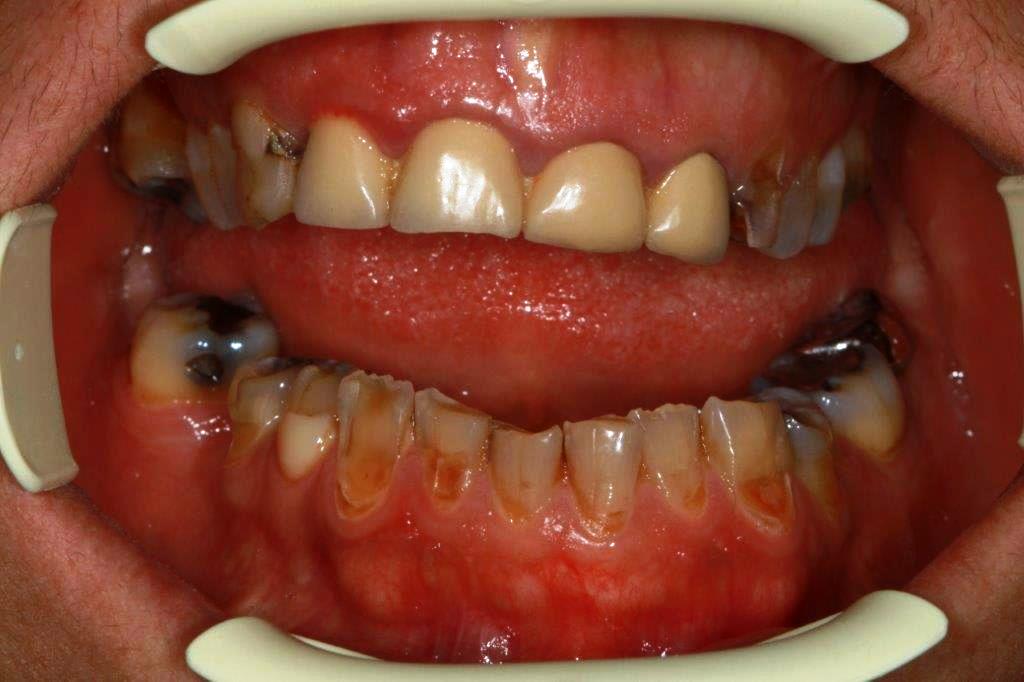

(tiens, les collets s'aligneront probablement tous seuls en repositionnant 21 22 23, celle là c'est enlaye qui me l'a apprise).

Je regardais comment retrouver le plan d'occlusion, je tirerais ma plaque de fox depuis les pointes canines mandibulaires, provisoires en postérieur, puis provisoires en postérieur maxillaire à la hauteur qui te convient, dans la même séance. Je laisse la béance antérieure créée jusqu'à la prochaine, elle devrait déjà se sentir un peu plus relax.

Séance suivante, horizontalisation (on n'a pas les repères du visage) de la ligne incisive mandibulaire, provisoires devant au maxillaire. Ca devrait permettre d'y voir plus clair.

sur ce cas , il y a 1 truc de particulier ,,ç est que les dents de devant sont solidarisées ( d'apres la pano )

ce qui voudrait dire que lorsque le bridge a été fait ,il y avait déjà la compensation osseuse et l'occlusion croisée .

imaginons que dans un 1er temps ,on coupe les solidarisations uniquement entre les centrales et que l'on gratte les couronnes pour arriver presqu'en en bout à bout de 21+22+23 . (le plus dur serait le préjudice esthétique de cette période .)

et en faisant des compo de glissement sur les dents antago du bas

ce serait déjà pas mal ( si pas d'ortho ,bien sur ).

à cela le fait de faire comme une élongation coronaire legere , l'os deviendrait plus souple et le rattrapage ultérieur par des ic serait plus facile .